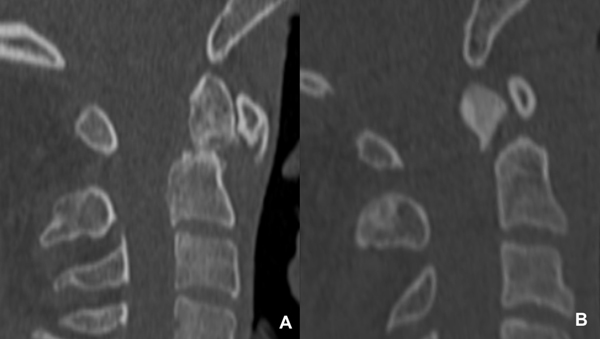

A modo ilustrativo se describen dos de los casos, uno en agudo con fractura y desplazamiento posterior del fragmento odontoideo, y la otra con pseudoartrosis y desplazamiento anterior (Figura 1).

Figura 1. TC de columna cervical - corte sagital.

A. Caso 1: Se observa la fractura del cuello de la odontoides, con listesis anterior del fragmento y bordes escleróticos. B. Caso 2: Se evidencia la fractura de odontoides tipo II con desplazamiento posterior del fragmento.